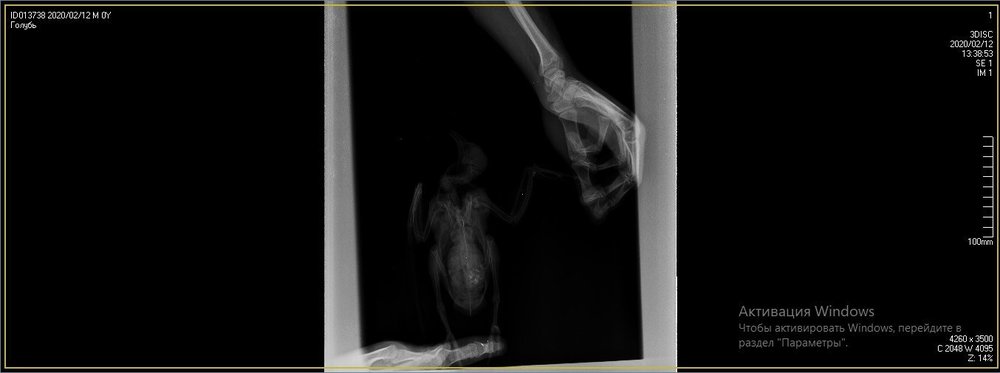

Duch Опубликовано 30 марта, 2020 #1 Опубликовано 30 марта, 2020 Здравствуйте! Приютился у нашего офиса, примерно 2 месяца назад, голубь и никак не улетал. Сделали вывод, что проблемы с крылом, т.к. левое он странно прижимал к себе. Положили в коробку, налили воды, насыпали гречи. Отогрелся спустя неделю, но крыло так и прижимал к себе. Предположили перелом крыла. Отвезли к орнитологу, сделали снимок (прикрепили к топику). Общий осмотр весьма позитивен, на снимке перелома нет. Выписали уколы витаминов и обезболивающих. Прокололи курс недели 2 назад - без изменений. На данный момент крыло так и прижимает к себе, огрызается, когда ему сыпят корм или доливают воды. Иногда клюёт и бьёт крылом, но только правым. Пока ждём выхода орнитолога из очередного отпуска, стараемся за ним ухаживать. В прошлую пятницу насыпали ему корм и подлили воды в плошку. Приехал в субботу вечером, дабы проведать. В итоге, он за целый день ничего не съел и не пил. На мои касания никак не реагировал: вжался в себя и стоял напуганный. Взял на руки, дабы осмотреть, как из под него показалась муха/слепень и тут же скрылась. Погуглил - оказывается, это - кровососки. Купил в ветеринарном отделе ампулу с препаратом, которую следовало разбавить 1,6л воды. Опрыскал её под крыльями, напоил водой из шприца и оставил так на день. Судя по корму, начал немного есть и пить. Кормплю гречкой, рисом и разваренным пшеном из шприца. Но сегодня обратил внимание, что он, когда клюёт сухой корм, как бы, промахивается и не может заглотить крупинку - гречка отскакивает в сторону и пытается еще раз захватить другую, но результат тот же. При всем при это, он четко видит мою руку и реагирует на неё соответствующим образом, т.е. слепоты нет Очень рассчитываю на вашу помощь! Ранее не имел опыта ухода за птицами

Виктория М. Опубликовано 30 марта, 2020 #2 Опубликовано 30 марта, 2020 (изменено) Здравствуйте. Нужен точный вес голубя. Помет желательно на листе белой бумаги. Проверьте нет ли наростов во рту , а также неприятныого запаха (кислого, тухлого). Кормить; 1 столовая ложка с горочкой 2 раза в день. Помимо гречи добавьте перловую крупу ,чечевицу или колотый горошек, пшеницу, овес без шелухи. Рис лучше уберите его можно но совсем немного. С каким препаратом ампула была? Все что обнаружил врач и все его назначения нужно выложить сюда на сайт, чтобы понимать чем вы лечили птицу. Какие витамины кололи какой курс и тд. Чтобы голубь начал нормально клевать зерно, в человеческой аптеке купите ноотропил таб или пирацетам . В вет аптеке нужно приобрести Фоспренил. Мух кровососок если вдруг еще обнаружите хорошо в тазике с водой вылавливать. Сажаете птицу в тазик с теплой водой, чтобы только голова на поверхности была, придерживаете аккуратно и так мин 10 -15 сидите с ним они начнут всплывать. Ваша задача не дать им вылететь из воды - передавить. Какое крыло он прижимает если смотреть на ренген? Изменено 30 марта, 2020 пользователем Виктория М.

маленький принц Опубликовано 1 апреля, 2020 #5 Опубликовано 1 апреля, 2020 (изменено) а можно рентген более крупный а не мелкий? у Вас на этой мелкой картинке трудно разглядеть подробности ВНОВЬ ЛЕТАТЬ и Здоровья Вашему голубю! чтобы узнавать новые ответы в Вашей теме нажмите пожалуйста наверху Вашей темы "подписаться" Изменено 1 апреля, 2020 пользователем маленький принц

Duch Опубликовано 1 апреля, 2020 Автор #6 Опубликовано 1 апреля, 2020 31.03.2020 в 01:36, Виктория М. сказал: Здравствуйте. Нужен точный вес голубя. Помет желательно на листе белой бумаги. Проверьте нет ли наростов во рту , а также неприятныого запаха (кислого, тухлого). Кормить; 1 столовая ложка с горочкой 2 раза в день. Помимо гречи добавьте перловую крупу ,чечевицу или колотый горошек, пшеницу, овес без шелухи. Рис лучше уберите его можно но совсем немного. С каким препаратом ампула была? Все что обнаружил врач и все его назначения нужно выложить сюда на сайт, чтобы понимать чем вы лечили птицу. Какие витамины кололи какой курс и тд. Чтобы голубь начал нормально клевать зерно, в человеческой аптеке купите ноотропил таб или пирацетам . В вет аптеке нужно приобрести Фоспренил. Мух кровососок если вдруг еще обнаружите хорошо в тазике с водой вылавливать. Сажаете птицу в тазик с теплой водой, чтобы только голова на поверхности была, придерживаете аккуратно и так мин 10 -15 сидите с ним они начнут всплывать. Ваша задача не дать им вылететь из воды - передавить. Какое крыло он прижимает если смотреть на ренген? Прикрепил назначение врача Во рту ничего подозрительного, как и в запахе. Может прозвучать неоднозначно, но он в вцелом, приятно пахнет) Ампула, которую разбавил в воде и опрыскивал 2 дня голубя под перья ( на тело) - "Дельцид" В воду окунали, правда держали минут 5. Ничего не всплыло и мы аккуратно его сушили феном, т.к. он сильно замёрз. Потом на форуме прочел, что насильное купание голубей недопустимо Глядя на рентген то, что раскрыто, т.е. правое. Делали снимок лёжа на спине, соответственно, по факту, это левое крыло

OFA Опубликовано 2 апреля, 2020 #25 Опубликовано 2 апреля, 2020 @Duch сама доктор смотрела рентген птицы? Что-то сказала? Нужно позвать нашего форумского доктора @Zosia посмотреть рентген. Может так разложена птица, но мне что-то кажется, что плечевой сустав не в порядке, но лучше пусть Зося посмотрит. Птица взрослая, клевать умеет, значит проблема или с жкт, или вертячка в такой форме.

маленький принц Опубликовано 2 апреля, 2020 #26 Опубликовано 2 апреля, 2020 @OFA рентген - в виде мелкой картинки просил автора залить рентген покрупнее

маленький принц Опубликовано 2 апреля, 2020 #30 Опубликовано 2 апреля, 2020 (изменено) @Duch вот рентген Вашего пациента Изменено 2 апреля, 2020 пользователем маленький принц

маленький принц Опубликовано 3 апреля, 2020 #33 Опубликовано 3 апреля, 2020 12 часов назад, Duch сказал: ну да, разве не его я прикрепил в прошлом сообщении? оно почему-то ужалось до мелких размеров если пойти по ссылке https://www.mybirds.ru/forums/uploads/monthly_2020_03/1SXcxYu_0rk.jpg.d7c82758490ddb04a65127b887286e57.jpg.28c0e1b9697a84b0cce71b1ee39e8254.jpg и открыть то видно что оно очень мелкое потому я скачав Ваш архив перезалил фото и увидев что оно ограничено по размерам дважды обрезав перезалил ещё раз